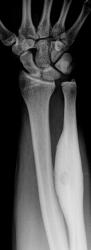

Татьяна Валентиновна представила интересный, классический случай "Остеоид-остеома".

Татьяна Валентиновна обращает внимание, что в данном случае имеют место, все классические признаки данного патологического процесса:

- выраженный гиперостоз;

- очаг разряжения - "гнездо";

- с более плотным включением - "яйцо в гнезде".